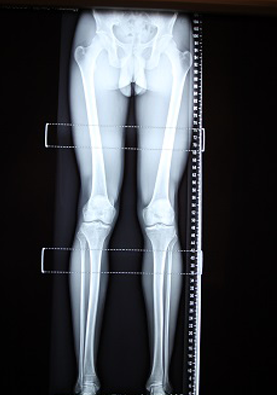

Above is the author’s full-length leg Xray films taken to determine any structural LLD. We are able to refer the client off for these films as required under a Medicare rebate.